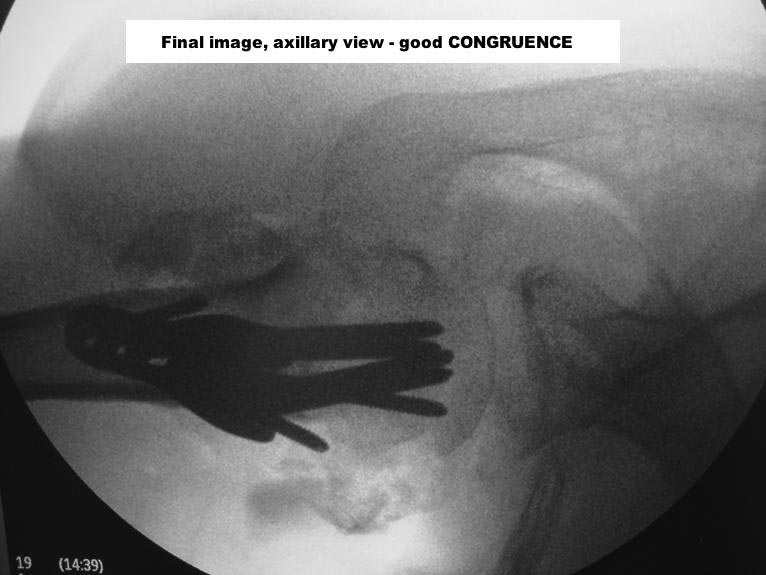

Пошли на операцию, будучи готовыми как к фиксации, так и к протезированию. Головка с краев была неполная, но для двух винтов места хватило. Сделали что-то вроде гемиартропластики собственной головкой. Бугорки фиксировали, как при эндопротезировании.

Снимки вот.

The nail looks a little proud. Will it not come in the way of mobilisation of the shoulder? What is your postop protocol in this case?

Dear Alex,

But if I should act as the devil’s advocate, I suppose, actually hope, the head was not totally avascular, there is some graft added, there might be either some faint impingement of the most proximal screw against the acromion or even the nail is a little proud cranial the bone ( or even the cartilage ? ). Maybe the end could be an avascular necrosis and it might be well tolerated ! Lots of bad possible outcomes and some possitive one.

In any case, you have procured yourself with the best of all possible morphologies should revision to a hemiarthroplasry is ever deemed to be done.

Ты нашу тактику знаешь, мы бы поставили пластину. Хотя без пластины, но получилось здорово!

Там видно ты применил Синтезовский MultiLoc гвоздь с screw in screw технику. Главное, ты собрал фрагменты и если понадобится следующие операции, тогда будет легче...